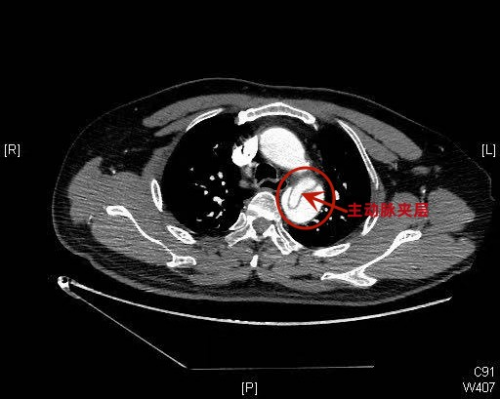

急诊科接诊医生、副主任医师赫留党介绍,患者蒋耀龙(化名)入院时面色潮红,表情痛苦,已经出现嗜睡症状,血压达175/107mmHg(正常范围90/60-120/80mmHg),心率98次/分,呼吸54次/分。经检查,患者被诊断出主动脉夹层Stanford B型,累及腹腔干及左髂总动脉、左肾动脉,情况危急,迅速转入急诊ICU,并请外周血管介入科进行会诊。外周血管介入科主任、主任医师赵扬程会诊后,结合患者当前的身体状况建议先积极控制血压,待收缩压稳定至100-130mmHg,平均动脉压维持在60-70mmHg-+;心率稳定至60次/分左右后再行介入手术。

2月8日凌晨,经过积极治疗,患者血压和心率稳定,被送进急诊介入室。赵扬程及外周血管介入科团队为患者在导管介入手术室全麻下进行胸主动脉、腹主动脉、双肾动脉、双髂动脉造影+主动脉覆膜支架植入术,顺利为患者拆除“不定时炸弹”。

赵扬程主任介绍,主动脉夹层是一种严重的心血管急危重症,是由于主动脉腔内的血液从主动脉内膜撕裂处进入主动脉中膜,使中膜分离,形成夹层血肿,并逐渐延伸剥离主动脉的内膜和中膜,随时可能造成血肿破裂,被称为“不定时炸弹”。常见的临床表现为突发的剧烈的胸痛或腰背部疼痛,疼痛性质为撕裂样或刀割样,并伴有血压升高。动脉夹层的病因和危险因素有高血压、动脉粥样硬化等。据了解,该患者没有进行过系统体检,患有高血压而不自知,这次发病前由于辅导孩子作业情绪激动、出现血压突发性急剧升高而造成了主动脉夹层。如果治疗不及时,严重可造成相应脏器缺血坏死、功能衰竭甚至死亡。